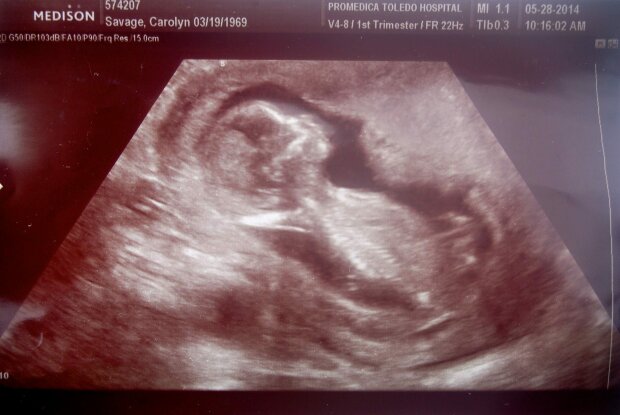

A právě tehdy, když se zdálo, že jejich životy nemohly mít více zatáček, možná nejpřekvapivější zprávy ze všech, se objevily na jaře 2014.

Carolyn nemohla uvěřit jejím očím, když se podívala na těhotenský test, který provedla doma v koupelně.

Může to být pravda?

Obrázek z google.com

Když moje omámená mysl analyzovala test, zoufale jsem si myslela, že to musí být špatně. Jsem neplodná. Během posledních dvou desetiletí jsem podstoupil nespočet léčebných postupů, včetně několika in vitro. Bylo mi 45 let. Teď nemohu být těhotná.

Syn Nicholas Winton Savage se narodil na podzim roku 2014 a najednou se rodina Carolyn a Sean Savage rozrostla na osm lidí - navzdory dvěma desetiletím bojům s neplodností.